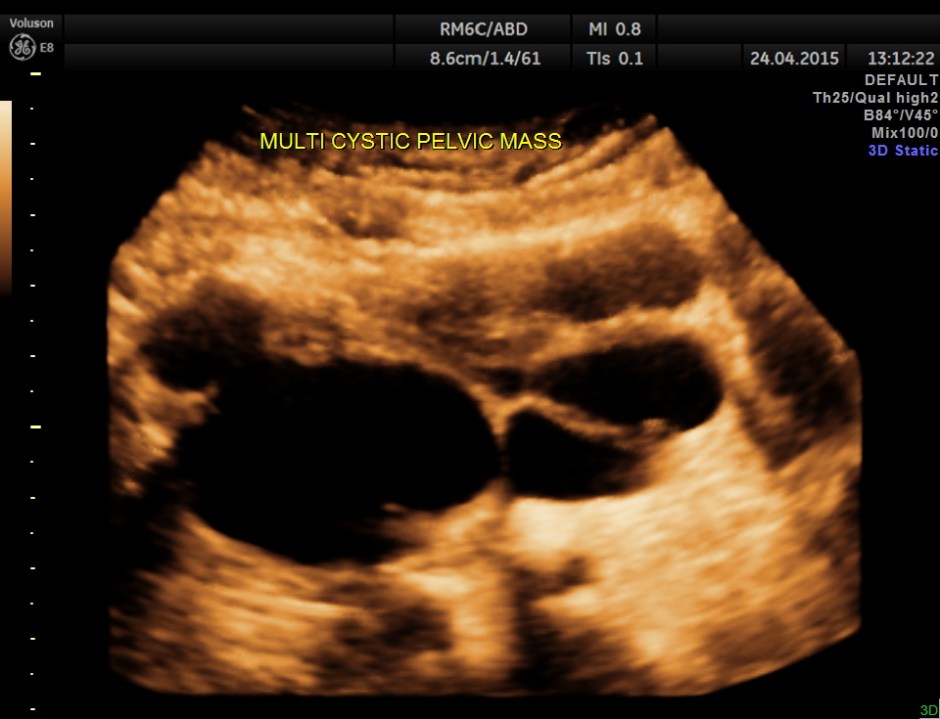

Superior angling shows a multi cystic pelvic mass – ? bladder diverticulae